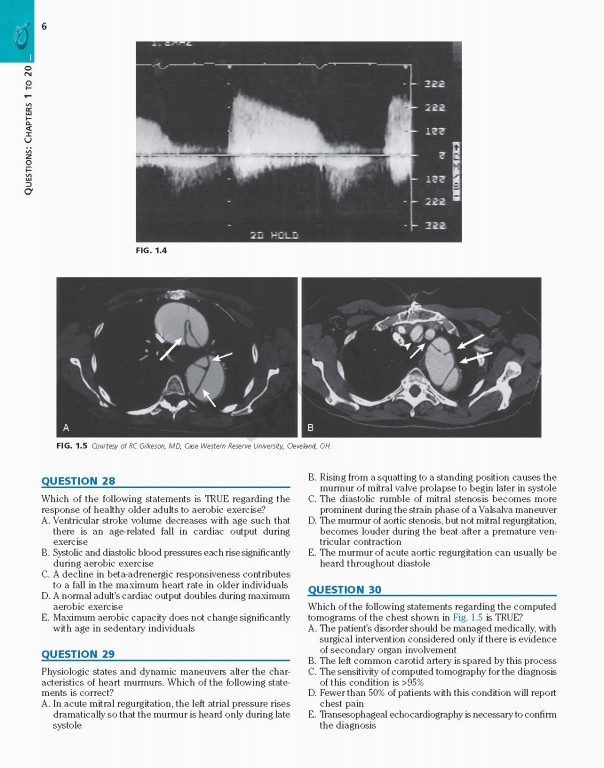

کتاب Braunwalds Heart Disease Review and Assessment 2019، بررسی و ارزیابی بیماری قلبی براونوالد ویراست یازدهم شامل تصاویر و تصاویر کاملاً رنگی که مطالعه شما را بهبود بخشیده و حفظ مواد پیچیده را بهبود می‌بخشد.

With more than 700 review questions derived from and keyed to the newly revised 11th Edition of Braunwald's Heart DiseaseBraunwald’s Heart Disease Review and Assessment, 11th Edition, is the perfect review tool for fellows, residents, and practitioners to prepare for board exams in cardiovascular medicine. Noted Harvard educator Dr. Leonard S. Lilly, with assistance from faculty and fellows at Brigham & Women’s Hospital, provides a thorough, clear, and concise overview of the entire field, helping ensure your mastery of all key aspects of today’s cardiology. This title is a one-stop resource for complete, authoritative coverage of the most important concepts in cardiovascular medicine – ideal for self-assessment, individualized study, and clinical practice.

• Contains full-color images and illustrations throughout, and numerous case studies that enhance your study and improve retention of complex material.